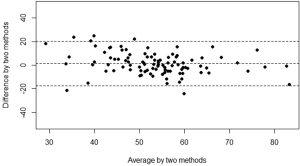

The mean kyphosis angle between the superior endplate of Th5 and the inferior endplate of Th12 of the sample as determined by the SpineAnalyzer® software measurements was 53° with a standard deviation of 10° and the mean kyphosis angle by manual measurements was 54° with a standard deviation of 12°. The Pearson’s correlation coefficient r between the manual measurements and the calculations derived from the SpineAnalyzer® software was 0.65 [95% confidence interval (CI): 0.53-0.75; P=2×10–13] (Figure 3). There was a substantial intraclass correlation with a coefficient of 0.64 for both consistency and absolute agreement (95% CI: 0.51-0.74 P=5×10–13 and P=4×10–13, respectively). The mean difference between methods was 1° (95% CI: –2°-4°) and not different from 0 (P=0.4). The interval between the 95% limits of agreement was –20°-17° where approximately half the individuals (47%) showed a difference of less than 5° and about three quarters less than 10° between the techniques (76%). The Bland-Altman plot did not show systematic biases of proportional error, dependency of variation on the magnitude of measurements, extreme outliers, systematic under- or overestimation (Figure 4).